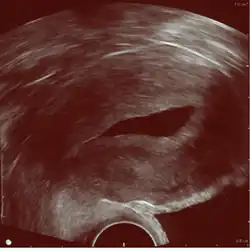

Gynecologic ultrasonography or gynecologic sonography refers to the application of medical ultrasonography to the female pelvic organs (specifically the uterus, the ovaries, and the fallopian tubes) as well as the bladder, the adnexa, and the recto-uterine pouch. The procedure may lead to other medically relevant findings in the pelvis.This technique is useful to detect myomas or mullerian malformations.

The examination can be performed by transabdominal ultrasonography, generally with a full bladder which acts as an acoustic window to achieve better visualization of pelvis organs, or by transvaginal ultrasonography with a specifically designed vaginal transducer. Transvaginal imaging utilizes a higher frequency imaging, which gives better resolution of the ovaries, uterus and endometrium (the fallopian tubes are generally not seen unless distended), but is limited to depth of image penetration, whereas larger lesions reaching into the abdomen are better seen transabdominally. Having a full bladder for the transabdominal portion of the exam is helpful because sound travels through fluid with less attenuation to better visualize the uterus and ovaries which lies posteriorly to the bladder. The procedure is by definition invasive when performed transvaginally. Scans are performed by health care professionals called sonographers, or gynecologists trained in ultrasound.